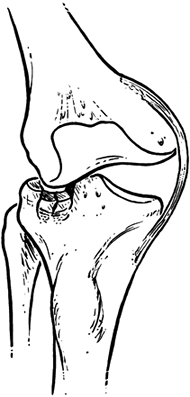

Fractures of the tibial plateau are caused by direct axial compression,

usually with a valgus (more common) or varus (less common) moment and

indirect shear forces. The anterior aspect of the femoral condyles is

wedge shaped; with the knee in full extension, the force generated by

the injury drives the condyle into the tibial plateau (47).

Figure 23.1. The classic mechanism of injury in tibial fractures is shown.

This is because the anatomic axis at the knee joint (which is normally

in 7° of valgus) as well as the mechanism of injury usually causes a

direct force from lateral to medial (30).